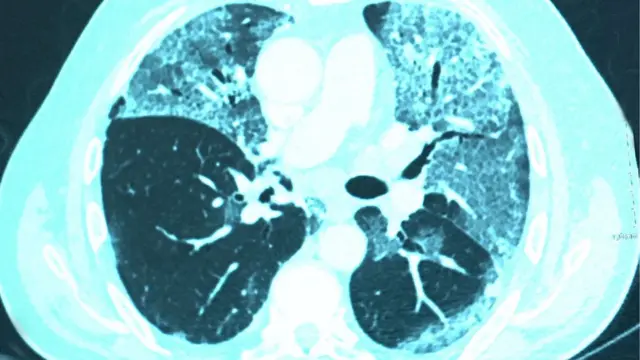

ব্রিটেনের রেডিওলজিস্টরা সেরে ওঠা রোগীদের প্রাথমিক স্ক্যান পরীক্ষার ভিত্তিতে বলছেন যারা কোভিডে বেশি অসুস্থ হচ্ছে তাদের দীর্ঘমেয়াদী ক্ষতির আশংকা বেশি।

"সেরে ওঠার ছয় সপ্তাহ পর যেসব রোগীর ফুসফুসের স্ক্যান আমরা দেখেছি, তার থেকে বোঝা যাচ্ছে যে, হাসপাতালে চিকিৎসা নেয়া ২০ থেকে ৩০ শতাংশ রোগীর ফুসফুসে ক্ষত তৈরির লক্ষণ পরিষ্কার," বলছেন ড. হেয়ার।

অন্য রেডিওলজিস্টরাও বিবিসিকে একই উদ্বেগের কথা বলেছেন, তারাও একই প্যাটার্ন দেখছেন।